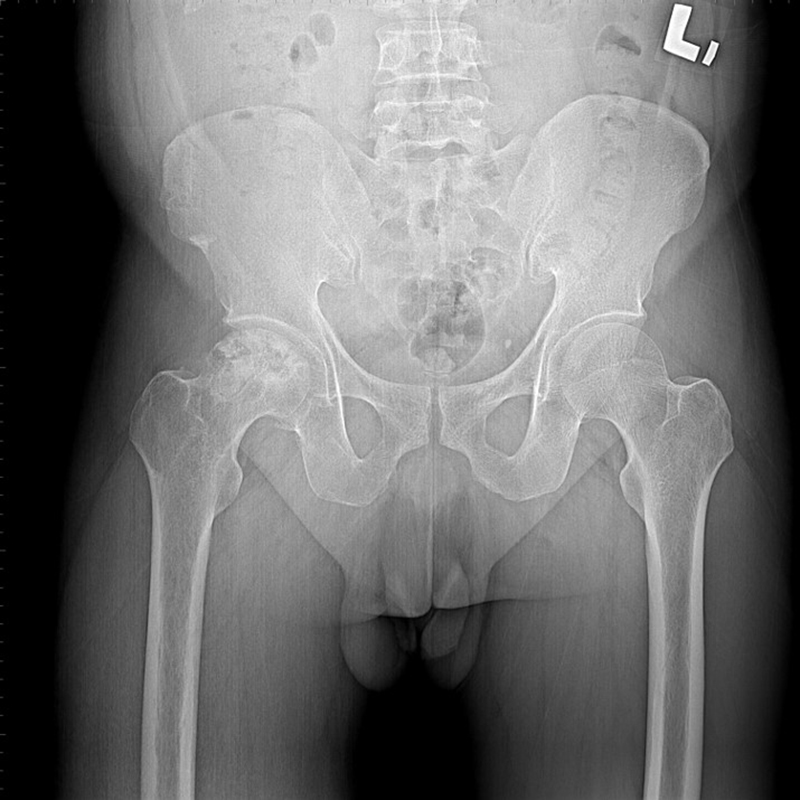

傳統髖關節置換 首頁 案例分享 髖關節手術 傳統髖關節置換 54歲蔡先生退化性關節炎 術前 術後 張女士 51歲 退化性關節炎(DDH先天發育不全 CROWE TYPE 2) 術前 術後 38歲林先生 退化性關節炎 術前 術後 72歲謝女士 退化性關節炎 術前 術後 71歲 謬女士 骨股頭壞死 術前 術後 50歲 郭先生骨股頭壞死 術前 術後 80歲 盧先生骨股頭壞死 術前 術後 林先生 37歲 術前 術後 邱女士 51歲 術前 術後 張女士 50歲 術前 術後